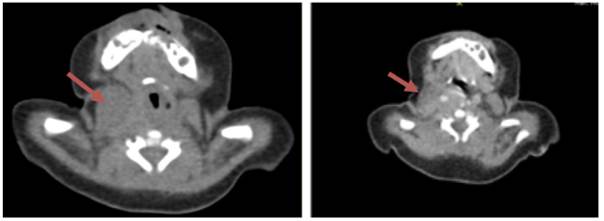

Antecedentes prenatales: Tercera gestación de la madre, controles prenatales #8, torch completo negativo, nacimiento por parto vaginal, presentación podálica a las 37 semanas, adaptación neonatal conducida 4/7/9, peso 2745 gramos, talla 48 cm, alta conjunta. No refiere fiebre, traumatismo o síntomas y signos respiratorios, sin antecedentes familiares. En el examen físico se encuentra talla :58 cm peso: 3.185 gramos FC:135 lpm FR:38 rpm T: 36.5c SaO2 98% ambiente, el examen de cuello evidenció presencia de masa firme, parcialmente móvil, de bordes regulares, sin cambio de coloración, sin calor al tacto y aparentemente una masa indolora de aproximadamente 1,5 * 2 cm, resto de examen físico dentro de parámetros normales. Se realizó ecografía de tejidos blandos que reportaron imagen ovalada, hipoecoica con escasa vascularización en su interior de 21x12x11 mm 10x13 mm, leve edema de piel y tejido celular subcutáneo adyacentes a la lesión descrita, por lo que se realizó tomografía computarizada (Figura 2).

Los hallazgos clínicos y radiológicos favorecieron el diagnóstico de Fibromatosis de colli, patología infrecuente, que no se tiene en cuenta puntualmente al examen del neonato al nacer, ni se incluye dentro de los signos de alarma a los padres, si notan asimetrías o dificultades para los movimientos de la cabeza del niño al darse el alta hospitalaria.